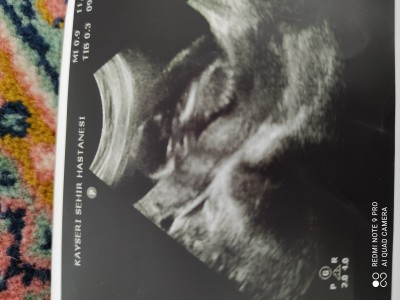

11 Şubat 2021 Hamilelik Dönemi Genel kategorisinde (64 puan) sordu

16.haftamizdayiz bacakları aşağıda olduğu için göremedim dedi doktor .ama sizce nedir cinsiyetini?

Gebelik haftası 16